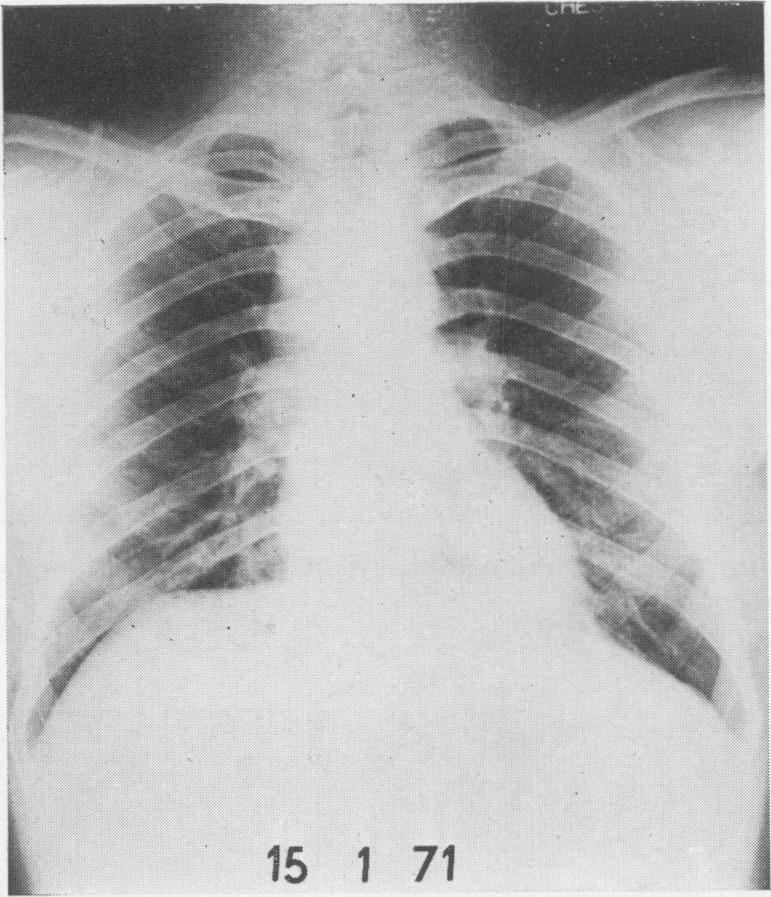

Mediastinoscopy: a diagnostic procedure in hilar and paratracheal lymphadenopathy.

Postgrad Med J. 1971 Nov;47(553):698-704. doi: 10.1136/pgmj.47.553.698.

Mediastinoscopy, in the skilled hands of a thoracic surgeon, is a safe, cosmetically accepted procedure with negligible complications, less than that reported in many series of scalene node biopsies. It has the advantage of yielding a much higher rate of diagnostic tissue, in all instances over 90%. In the cases of tuberculosis it enabled an organism to be isolated and sensitivities obtained. It has also revealed a group of cases with findings, a further study of which may increase our understanding, assessment and management of patients presenting with hilar and/or paratracheal lymphadenopathy.